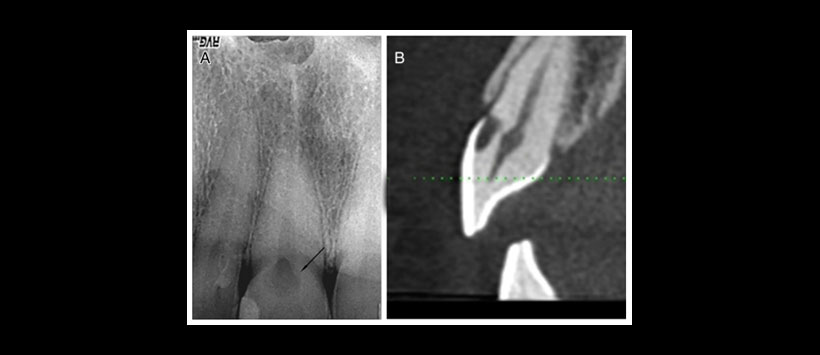

Figura 3: (A) Radiografía periapical típica de una imagen radiolúcida proyectado a nivel cervical en cara libre. (B) Una exploración CBCT que muestra reabsorción cervical invasiva a nivel cérvico-vestibular.